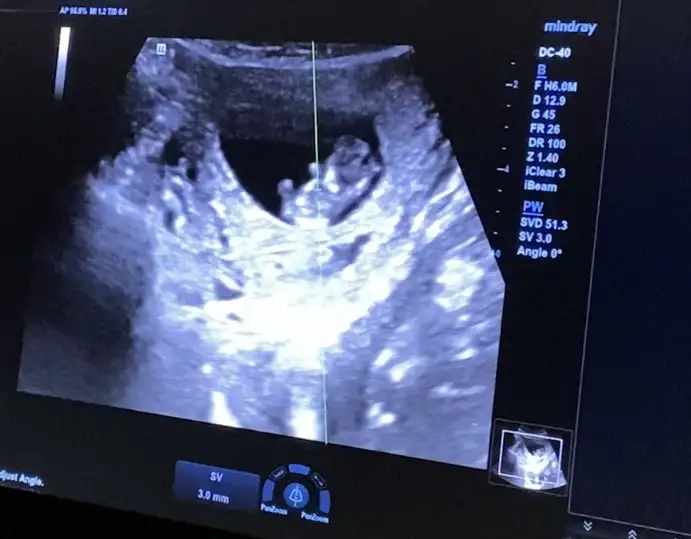

Cinsiyet tahmini için ultrason görüntüsü paylaşıyorum, yorumlarınızı merak ediyor, heyecanla bekliyorum.